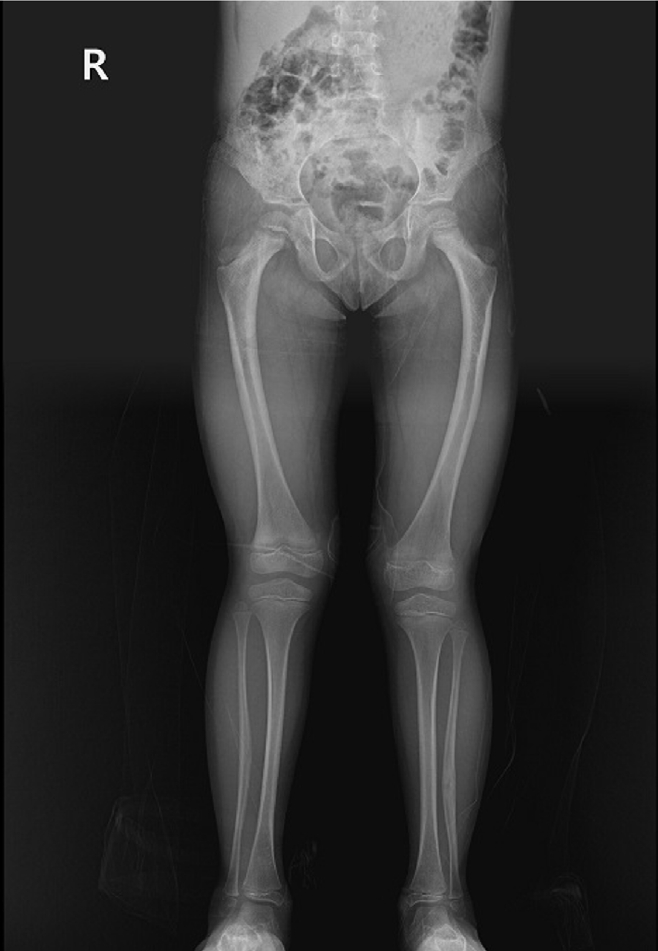

Fig. 6.

Prefracture radiographs of a 73-year-old female patient who subsequently presented with a femoral shaft fracture demonstrating cortical hypertrophy and microfracture. (A) Anteroposterior view. (B) Lateral view.

Case 3: distal locking screw of intramedullary nail

A 73-year-old female patient visited our emergency room complaining of pain in the left thigh that had begun approximately a month ago. She had undergone intramedullary nail fixation for a left femoral intertrochanteric fracture 9 years prior and reported no history of recent trauma. The patient had initially sought treatment at another hospital for her left thigh pain and was discharged after conservative management. However, she experienced sudden severe pain accompanied by a breaking sound while walking. Upon examination, her BMD at the L3‒4 levels was noted to be ‒3.1. The patient also had a history of rheumatoid arthritis and hypertension, with no history of cancer. Radiographic evaluations, including anteroposterior and lateral views of the left femur, revealed a left femoral shaft fracture and metal breakage at the distal locking screw fixation site of the previously inserted intramedullary nail. Notably, when the patient first visited the other hospital, a hypertrophy and microfracture were observed at the lateral site of the distal locking screw insertion (Figs. 6, 7). Following the diagnosis, the patient underwent intramedullary fixation using a long nail. Subsequent follow-up evaluations indicated successful bone union at the fracture site.